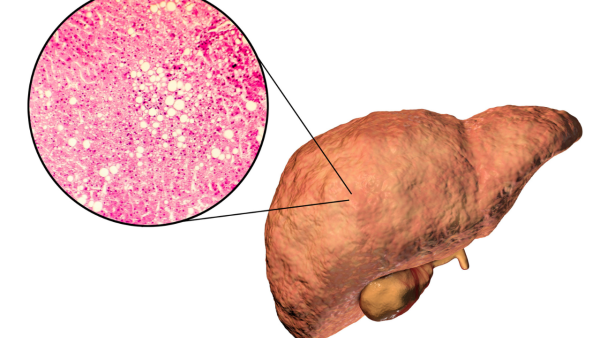

Fatty liver disease , especially NAFLD , has become a prevalent health concern across the globe, and the burden keeps growing. It occurs when the liver develops inflammation and possibly damage, due to a buildup of too much fat in it. Vitamin B12 deficiency has emerged in recent years as one of the major factors that may be of importance for its development and progression.

Vitamin B12 is highly essential in the body's metabolic processes, such as fat breakdown and liver health maintenance. The liver cannot handle fat processing and its exportation when the levels of B12 are low; hence, it deposits that fat within liver cells. The deposition promotes inflammation that can cause scarring and dysfunction of the liver if left unmanaged. Several studies have reported that levels of vitamin B12 are usually low in NAFLD patients compared to individuals with normal health.

The deficiency influences homocysteine levels, an amino acid molecule associated with oxidative stress and liver damage, further worsening the health of the liver. Supplementation with vitamin B12 decreases homocysteine levels and can improve liver enzymes, potentially slowing down the progression of the disease.

Research on vitamin B12 and fatty liver disease is ongoing and changing. Some trials have shown promising benefits of supplementation with vitamin B12 on liver enzymes and metabolic markers, while others have called for larger studies to firmly establish these effects. The association between B12, homocysteine, and liver health becomes relevant because it explains exactly how vitamin deficiency leads to oxidative stress and eventual tissue damage. Future studies will likely focus on optimizing B12 dosing and combination therapies with other vitamins, including folate, to maximize liver protection. These are hopeful signs toward novel strategies in the management of NAFLD and its related disorders. Vitamin B12 deficiency is a silent yet very serious cause of fatty liver and possibly gallstones.

According to NAFLD is a very common health problem in developed countries. Research is now focusing on the role of vitamins especially B12 in the fat buildup in the liver. Vitamin B12 is important for many cell processes including DNA synthesis and fat metabolism.